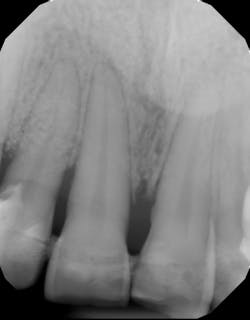

Tables 1–3 present actual treatment cost differences between the patient who opts to “save” the natural tooth (treatment plan A) and the one who chooses to “remove” the tooth via extraction and placement of an implant (treatment plan B). These fees vary according to geographic location and represent insurance codes from New York City, Los Angeles, Chicago, and Dallas.

Another scenario that took place in a private practice with actual dollar amounts can be seen in treatment plan C. This patient had already paid for treatment plan B in the $5,000–$7,000 range and subsequently presented to the practice with moderate peri-implantitis. In addition to the money the patient had already invested, she would now be responsible for the financial costs of treatment plan C.

In conclusion, there are many factors to consider when deciding between saving the natural dentition and extracting and placing implants. All parties must consider the long-term economic impact on the patient as well as the long-term success rates of the treatment. Both implants and periodontal therapy to save natural teeth have high initial success rates, with implants usually incurring initial costs. However, when looking at long-term retention rates, natural teeth often demonstrate fewer complications and have a smaller financial impact when correction is needed.17